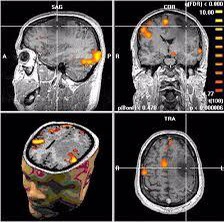

Con estos gradientes podemos seleccionar el «corte» que deseamos visualizar y codificar en fase y frecuencia los spines en dicho corte. Las imágenes por resonancia magnética (cortes) pueden almacenarse o imprimirse y un examen produce docenas e incluso cientos de imágenes de la zona examinada. Mejor que si estuviésemos abriendo un cadáver

Actualmente, las imágenes obtenidas por resonancia magnética guían a los cirujanos en operaciones cerebrales, detectan síntomas de infartos cerebrales y nos han ayudado a esclarecer el funcionamiento del cerebro.Nada de esto hubiera sido imaginable en aquella época oscura de la novela de Noah Gordon, recientemente llevada a pantalla sobre la Europa sombría y oscura del siglo XI hasta la fascinante Persia, con el mítico maestro Avicena